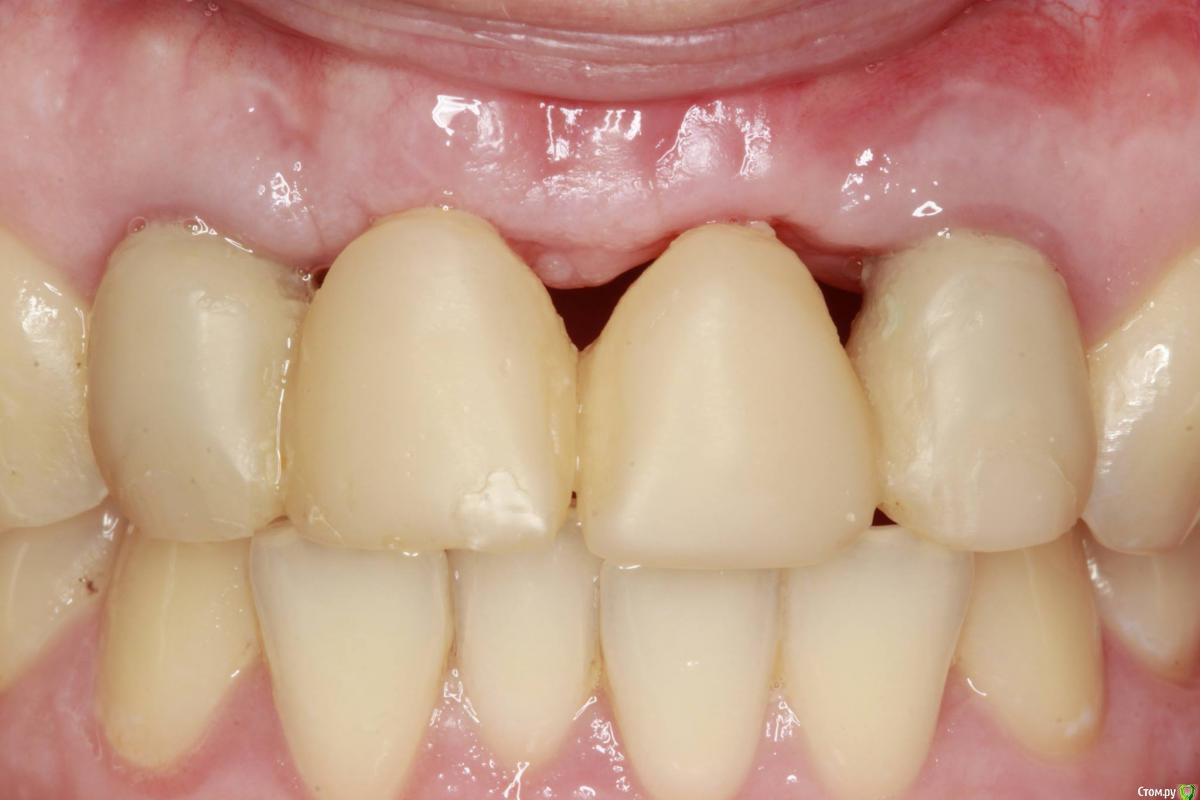

Популярный пост Ст@ся Опубликовано 7 июня, 2016 Автор Популярный пост Поделиться Опубликовано 7 июня, 2016 21 Ссылка на комментарий

ввассилюй Опубликовано 7 июня, 2016 Поделиться Опубликовано 7 июня, 2016 на последнем фото зубы новые? 1 Ссылка на комментарий

Ст@ся Опубликовано 7 июня, 2016 Автор Поделиться Опубликовано 7 июня, 2016 Нет, старые 1 1 Ссылка на комментарий